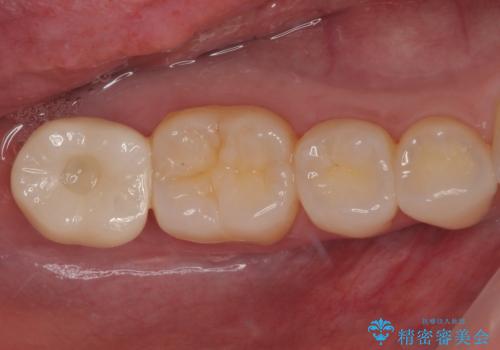

- セラミッククラウン

- 2009~2025年6月

- 000本

- セラミックインレー